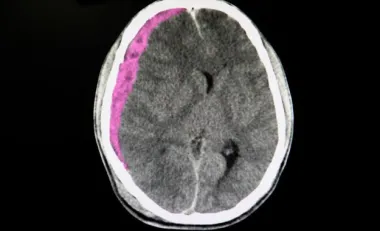

symptômes d’un AVC chez la femme

Quels sont les symptômes d’un AVC chez la femme ?